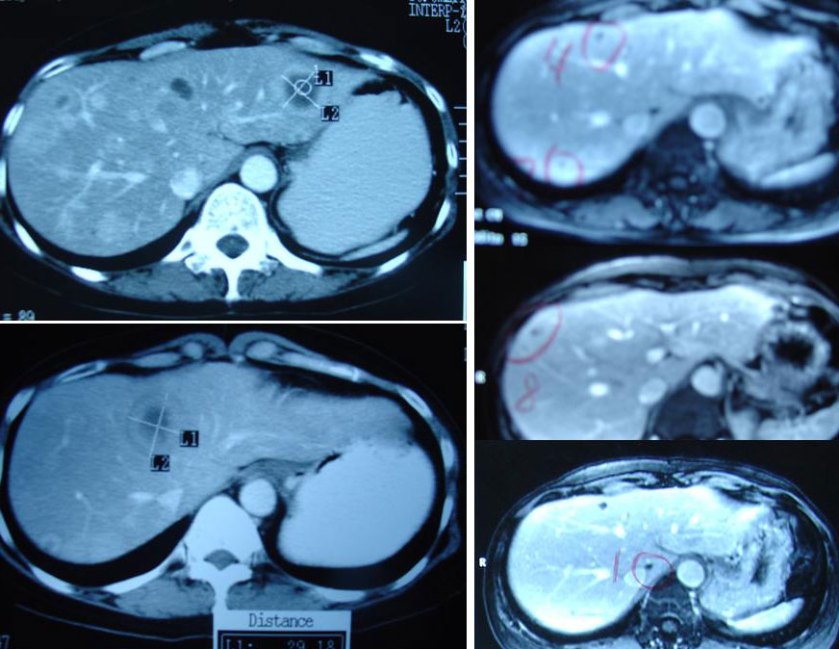

She suffered headaches, nausea and had very low blood pressure. Fransiska went back to her oncologist in August 2008. A scan showed the cancer had spread to her brain. A CT scan of the abdomen showed:

- metastasis in both hepatic lobes. The largest lesion in the left lobe measures 2.0 x 1.8 cm and the largest in the right lobe measures 1.5 x 1.4 cm.

- Sclerotic focus in the T12 vertebral body is stable.